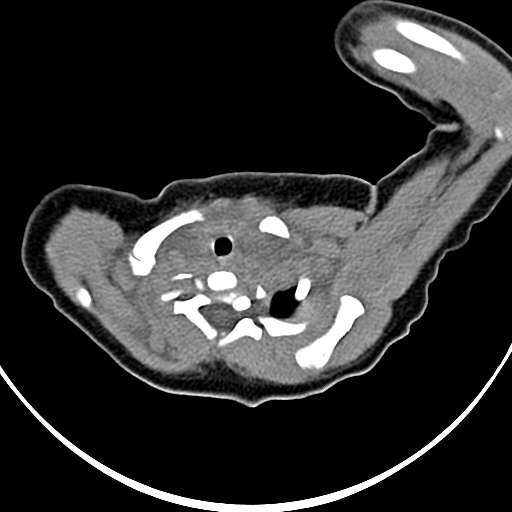

标题: PED1779:左侧锁骨下方异常密度影 请指教 [打印本页]

标题: PED1779:左侧锁骨下方异常密度影 请指教

患者,男,1月,出生后一月,无明显诱因出现颈部左前方肿块。体检:左侧颈部轻度凸起包块,触之较硬。

病灶与左侧胸锁乳突肌分界不清,软组织密度,不似囊性改变,从病人的年龄及病变性状首先要除外先天性斜颈(肌性斜颈)可能。

作者: 祥云 时间: 2009-3-7 04:30

左侧胸锁乳突肌肿大,考虑产伤所致

胸锁乳突肌挛缩(斜颈)?